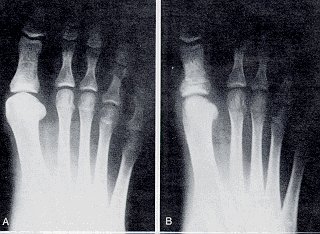

Deformity of hallux abducto valgus has a hallux abductus angle of 5° to 20°, and a first intermetatarsal angle of 6° to 8°. In mild hallux abducto valgus deformities, the joint surface is generally congruous (Fig. 1).

Figure 1

An example of mild HAV deformity.

1. Preoperative view.

2. The same patient one year after surgery.